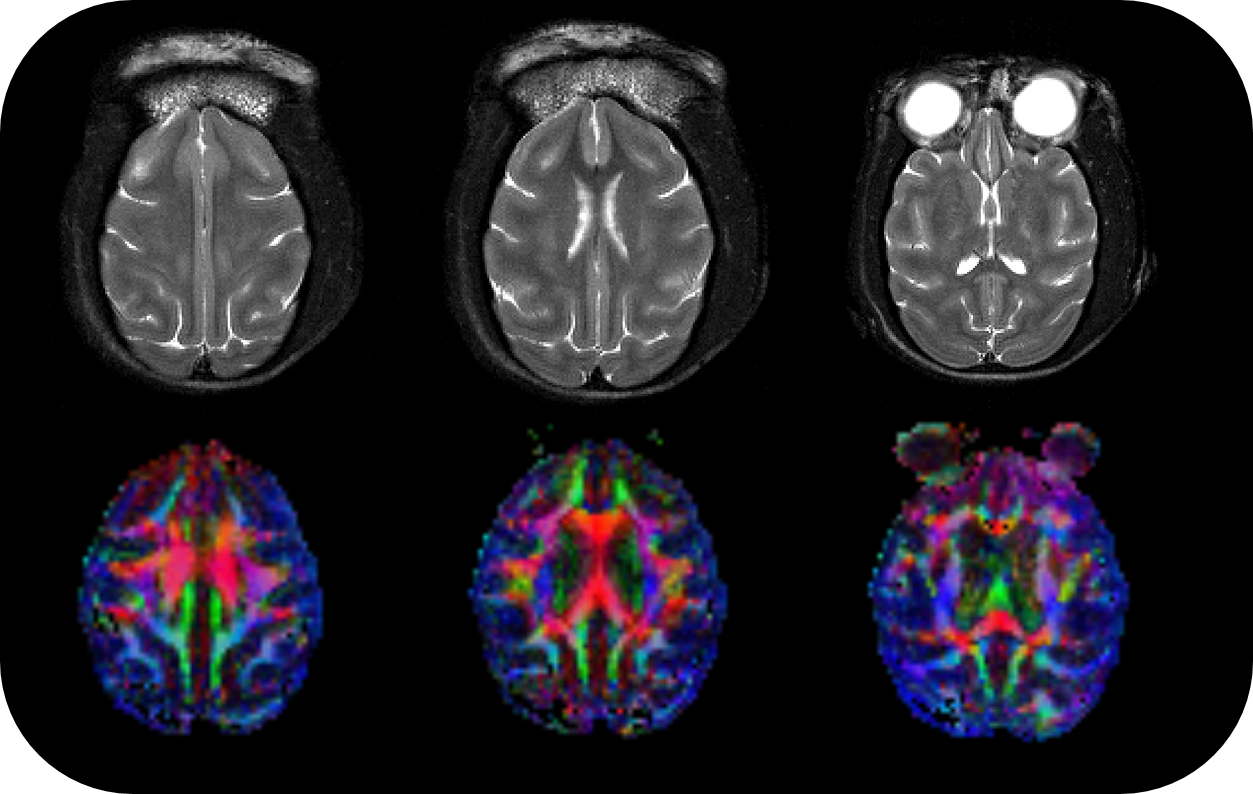

BioSpec 70/30 and 94/30

Studies with intricate set-ups or on animals up to the size of rabbits can be conducted with the extremely physically stable, 30 cm bore size BioSpec 70/30 and BioSpec 94/30.

• MRI sequence portfolio of more than 1,000 sequence variations, including wireless cardiac imaging using navigator based IntraGate methods with cartesian or radial readout, as well as short echo time imaging, such as UTE and ZTE

PET Insert or Inline

Upgradable with state-of-the-art PET module as inline or insert with full field of view and accuracy offers real, homogeneous sub-millimetric volumetric PET resolution and quantification in all three axes, in the entire field of view. This is possible due continuous crystal detectors with SiPM technology and true depth of interaction 3D precision equivalent to 10+ layer pixelated crystal detectors.